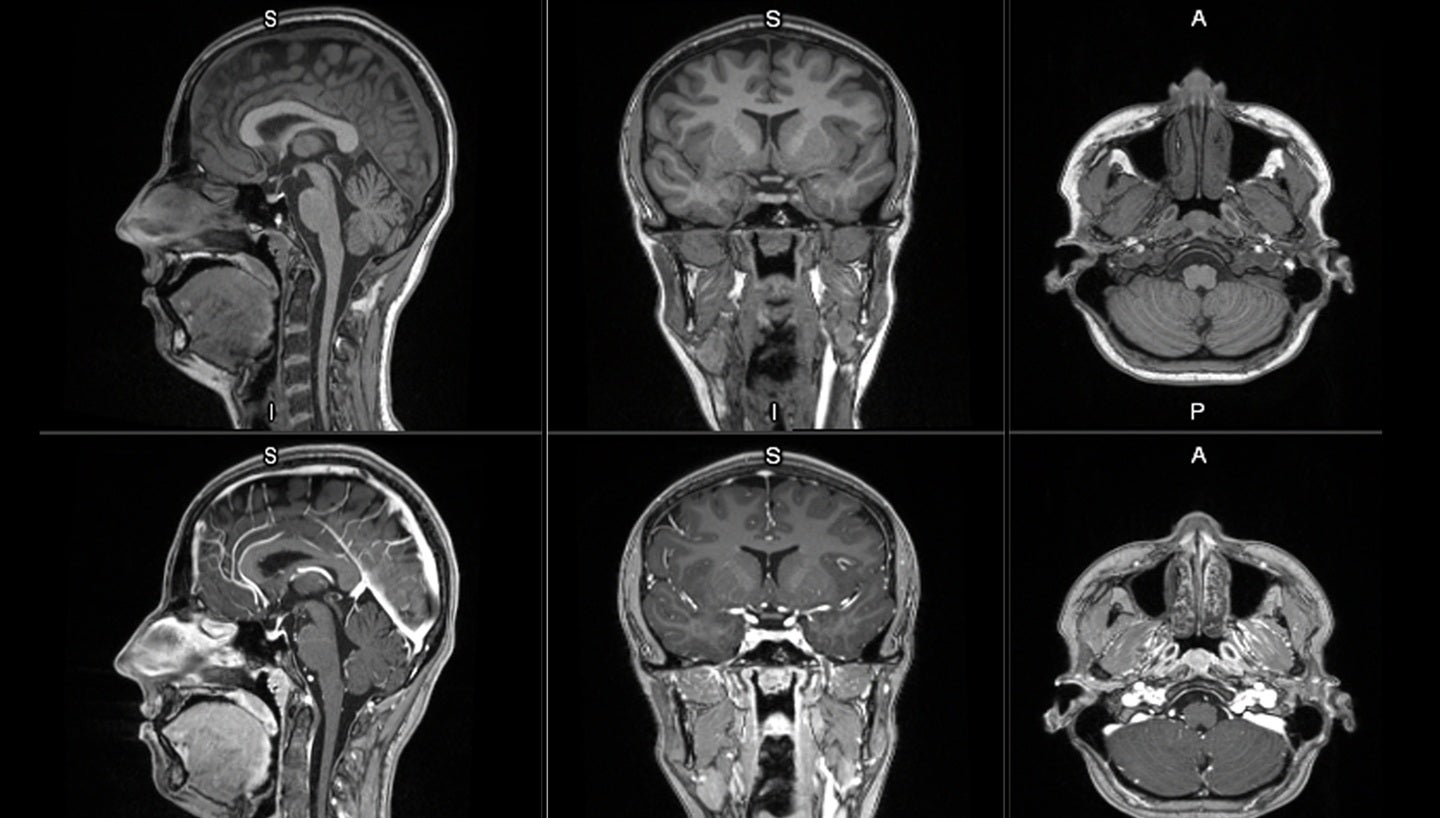

GE HealthCare has dosed the first patient in its Phase II/III LUMINA clinical trial for the investigational manganese-based MRI contrast agent, mangaciclanol.